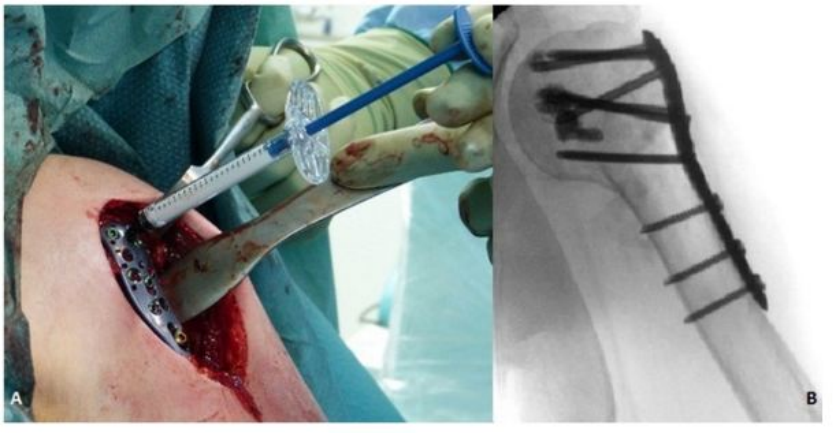

丙烯酸骨水泥在骨科手术中发挥着重要作用,其中聚甲基丙烯酸甲酯(PMMA)已从最初的眼科和牙科领域,扩展至骨科领域,并广泛地应用于假体内植物的固定、肿瘤和椎体骨折的治疗。骨质疏松性股骨近端骨折使用骨水泥强化的内固定系统可以减少约50%的失败率,主要适应症是不稳定型脆性骨折[24]。对骨科医生来说,骨量减少的肱骨近端骨折患者的治疗充满挑战。尽管内植物的设计不断改良,但螺钉或螺旋刀片在肱骨近端松质骨内的把持力仍然不足,而这也是内固定失败最主要的原因之一。骨水泥强化技术即将骨水泥注入肱骨头内,填补了内植物与肱骨头之间的空隙,从而增强内植物的把持力[25]。近年来,采用中空的螺钉结合角度稳定钢板系统,骨水泥可以通过中空的螺钉注入,达到骨水泥强化的效果[25]。骨质疏松性胫骨平台骨折与髋部骨折、肱骨近端骨折都不同,它是由于垂直应力直接作用于骨量减少的软骨下骨组织,造成关节面的凹陷和/或劈裂;其经典手术方式是通过植入自体或异体松质骨,支撑重建关节面[26]。但是,自体或异体松质骨在骨折愈合阶段,无法提供足够的力学支撑,造成关节面塌陷,利用骨水泥强化技术可能改善上述情况。